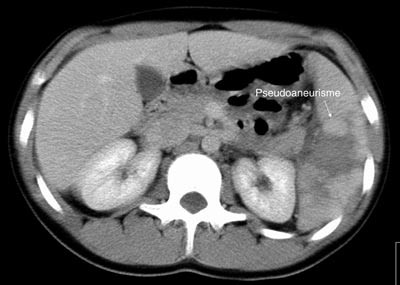

Pasient 2. En 20 år gammel mann ble utsatt for en trafikkulykke. Han var komatøs og ble intubert på skadestedet. CT-undersøkelse ved Ullevål universitetssykehus viste venstresidig pneumothorax og costafrakturer. I milten forelå en laserasjon kaudalt (skadegrad III), men normale funn i hilusnivå (e-fig 4). Pasienten ble observert og overflyttet til lokalsykehus etter tre dager. Seks dager etter traumet ble det gjort en CT-kontroll med arteriell kontrastfase. Denne viste en tilkommet, høytattenuerende lesjon ved milthilus, forenlig med et pseudoaneurisme (e-fig 5). Pasienten ble flyttet tilbake til Ullevål universitetssykehus hvor det ble utført angiografi med embolisering (e-fig 6). Ultralydkontroll samme dag viste opphørt sirkulasjon i lesjonen. Tre dager senere ble pasienten utskrevet.

I litteraturen er det beskrevet redusert sensitivitet og spesifisitet for pseudoaneurismer ved CT-undersøkelse sammenholdt med angiografi (8), men undersøkelsene er som oftest kun gjort i venøs kontrastfase. I flere studier er det benyttet forsinkelse fra kontrastinjeksjon til bildeopptak på mellom 70 og 85 sekunder som tilsvarer sen eller venøs kontrastfase (1, 9, 10). CT-bildene fra undersøkelsen av pasient 1 illustrerer at dette kan vanskeliggjøre diagnostikken. I tillegg er det viktig å vite at vaskulære lesjoner kan presentere seg forsinket. Det viser bildene av pasient 2. CT-undersøkelse i arteriell og venøs fase etter 5 – 7 dager i tillegg til undersøkelse ved innkomst er derfor anbefalt (2, 6).